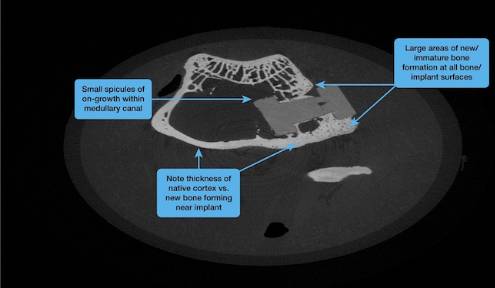

材料供应商索尔维(Solvay)宣布,医疗设备公司DiFusion Technologies选择了它的Zeniva ZA-500聚醚醚酮(PEEK)作为其ZFUZE骨传导材料的基础聚合物,用于脊椎植入物。近期,在DiFusion的测试中,该化合物展示了所有骨植入物表面的大面积新骨生成区,这一结果在北美脊柱学会(North American Spine Society)会议上得到了分享。